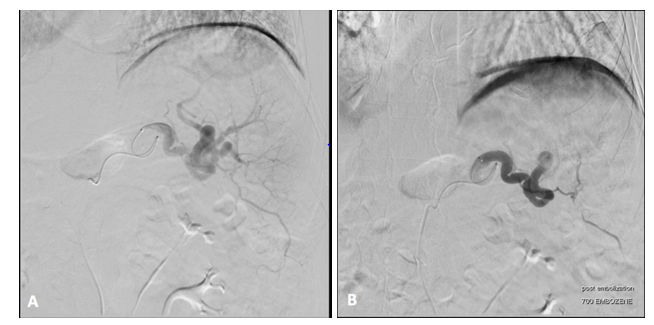

A 71-year old man presented to the emergency department with acute onset massive hematemesis and epigastric pain. He denied jaundice, NSAID use or prior hematemesis. Relevant medical history included heavy tobacco use in the past but denied alcohol use. He presented hypotensive with tachycardia. He had tenderness in the epigastric and left upper quadrant without peritoneal signs. Hemoglobin was decreased at 8.3g/d from baseline 12. Total bilirubin and liver function tests were within normal limits. Contrast enhanced CT of the abdomen and pelvis done in the ER showed splenic vein thrombosis (Figure 1A, arrowhead), gastric varices (Figure 1B, circled) with active hemorrhage noted, and a 5cm mass in the pancreatic tail extending into the splenic hilum (Figure 1C, arrow). No changes of cirrhosis were noted in the liver, but possible peritoneal implants were noted. Given the active gastric variceal hemorrhage and the patient’s instability, emergent endoscopy was deferred. The patient was stabilized in the ICU. Given the suspected metastatic nature of his pancreatic cancer, the patient underwent successful splenic artery embolization using 700micron embozene particles (Figure 2) and the patient did not experience any further episodes of hematemesis. After he was stabilized tissue diagnosis of metastatic pancreatic adenocarcinoma was confirmed with peritoneal biopsy. Other labs were notable for an elevated CEA at 45.5ng/mL and CA 19-9 of >10,000U/mL.

Figure 1 Abdominal CT enhanced with contrast. (A) Splenic vein occlusion (arrowhead) and perisplenic varices (arrow) (B) Gastric varices related to splenic vein occlusion (circled). (C) Coronal view of pancreatic mass (arrow).